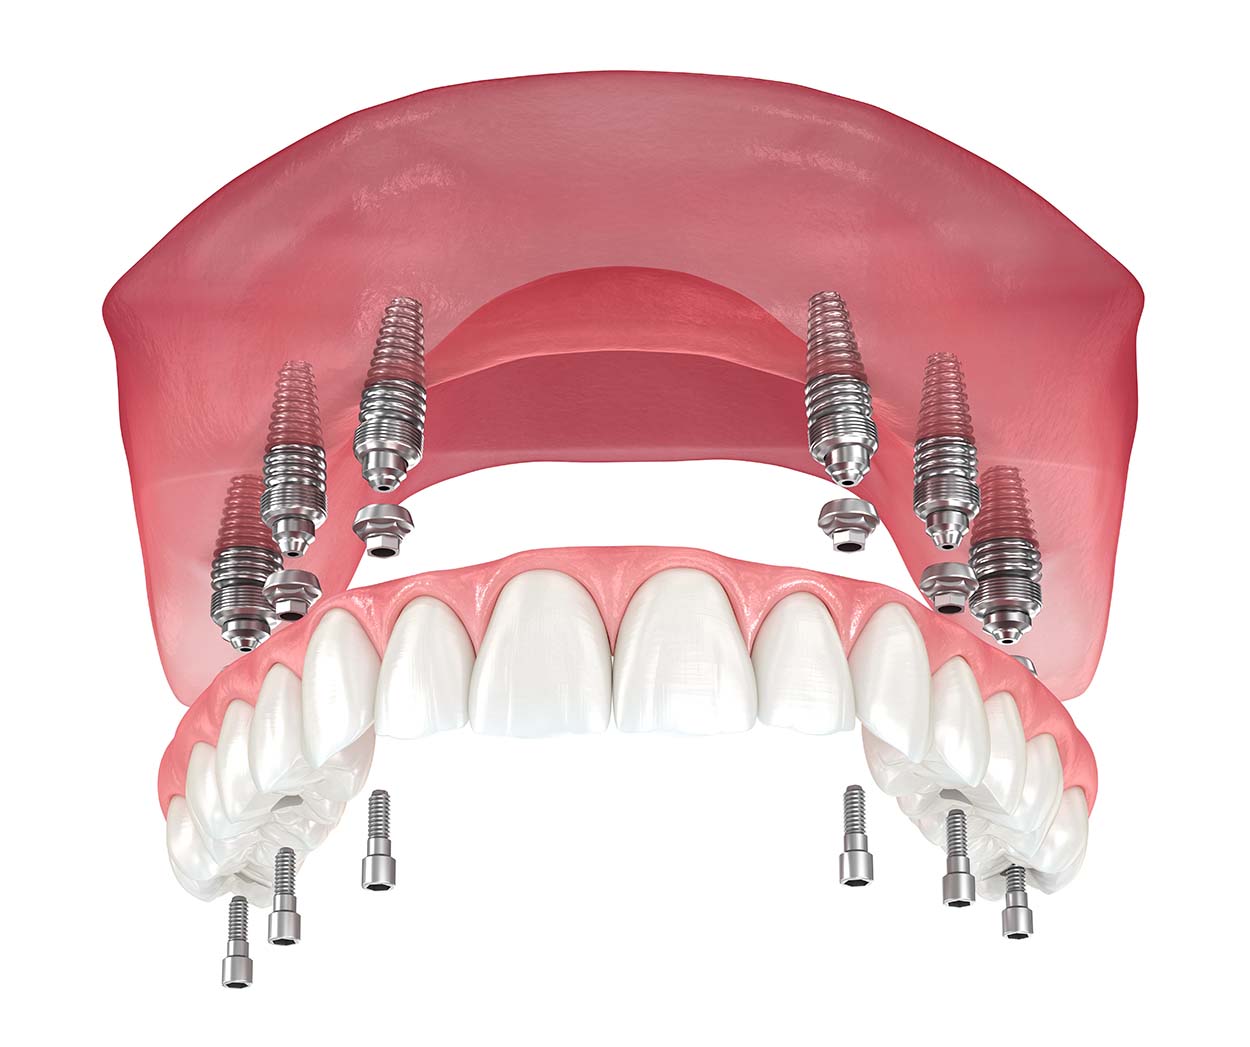

В большинстве случаев всё, что потребуется пациенту, это установка только шести имплантов. Это даст стоматологу возможность поставить несъёмный протез. В таком случае пациент будет чувствовать себя совершенно комфортно — его искусственные зубы будут так же функциональны, как и родные.

Помимо этого, возможна имплантация по другой методике. Используя её, можно поставить несъёмные зубные протезы даже на челюсть, на которой полностью удалены или утрачены зубы. При этом всё, что потребуется сделать, это установить четыре искусственных зуба.